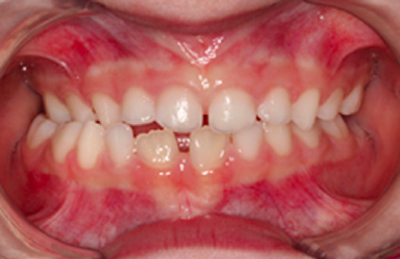

Caso 1

As imagens abaixo ilustram um caso de mordida cruzada anterior tratado com ortopedia facial. Observe que os incisivos superiores, que se encontravam inicialmente atrás dos incisivos inferiores, passou a ocluir corretamente.